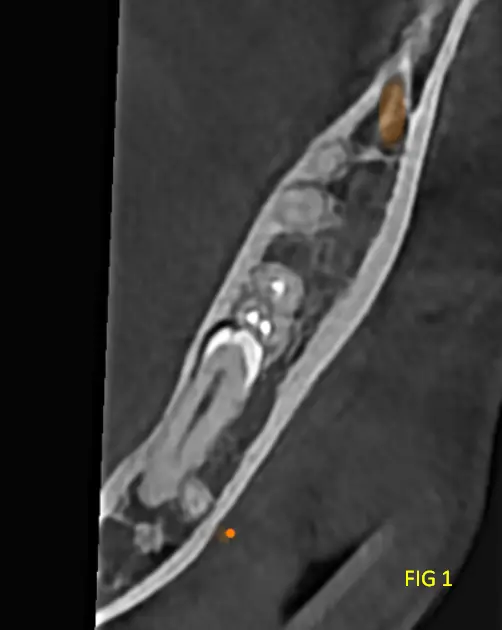

En las reconstrucciones 3D y cortes multiplanares (ver Fig 1, 2 y 3) se observa lesión oseteolítica extensa con ausencia de una capsula definida, ubicada en el cuerpo mandibular, lado izquierdo, zona de premolares.

Presenta tabiques óseos finos que delimitan compartimentos irregulares con expansión y adelgazamiento de las corticales óseas, con áreas de compromiso cortical. La relación cercana con el conducto dentario inferior, sin evidencia clara de invasión, pero con desplazamiento.